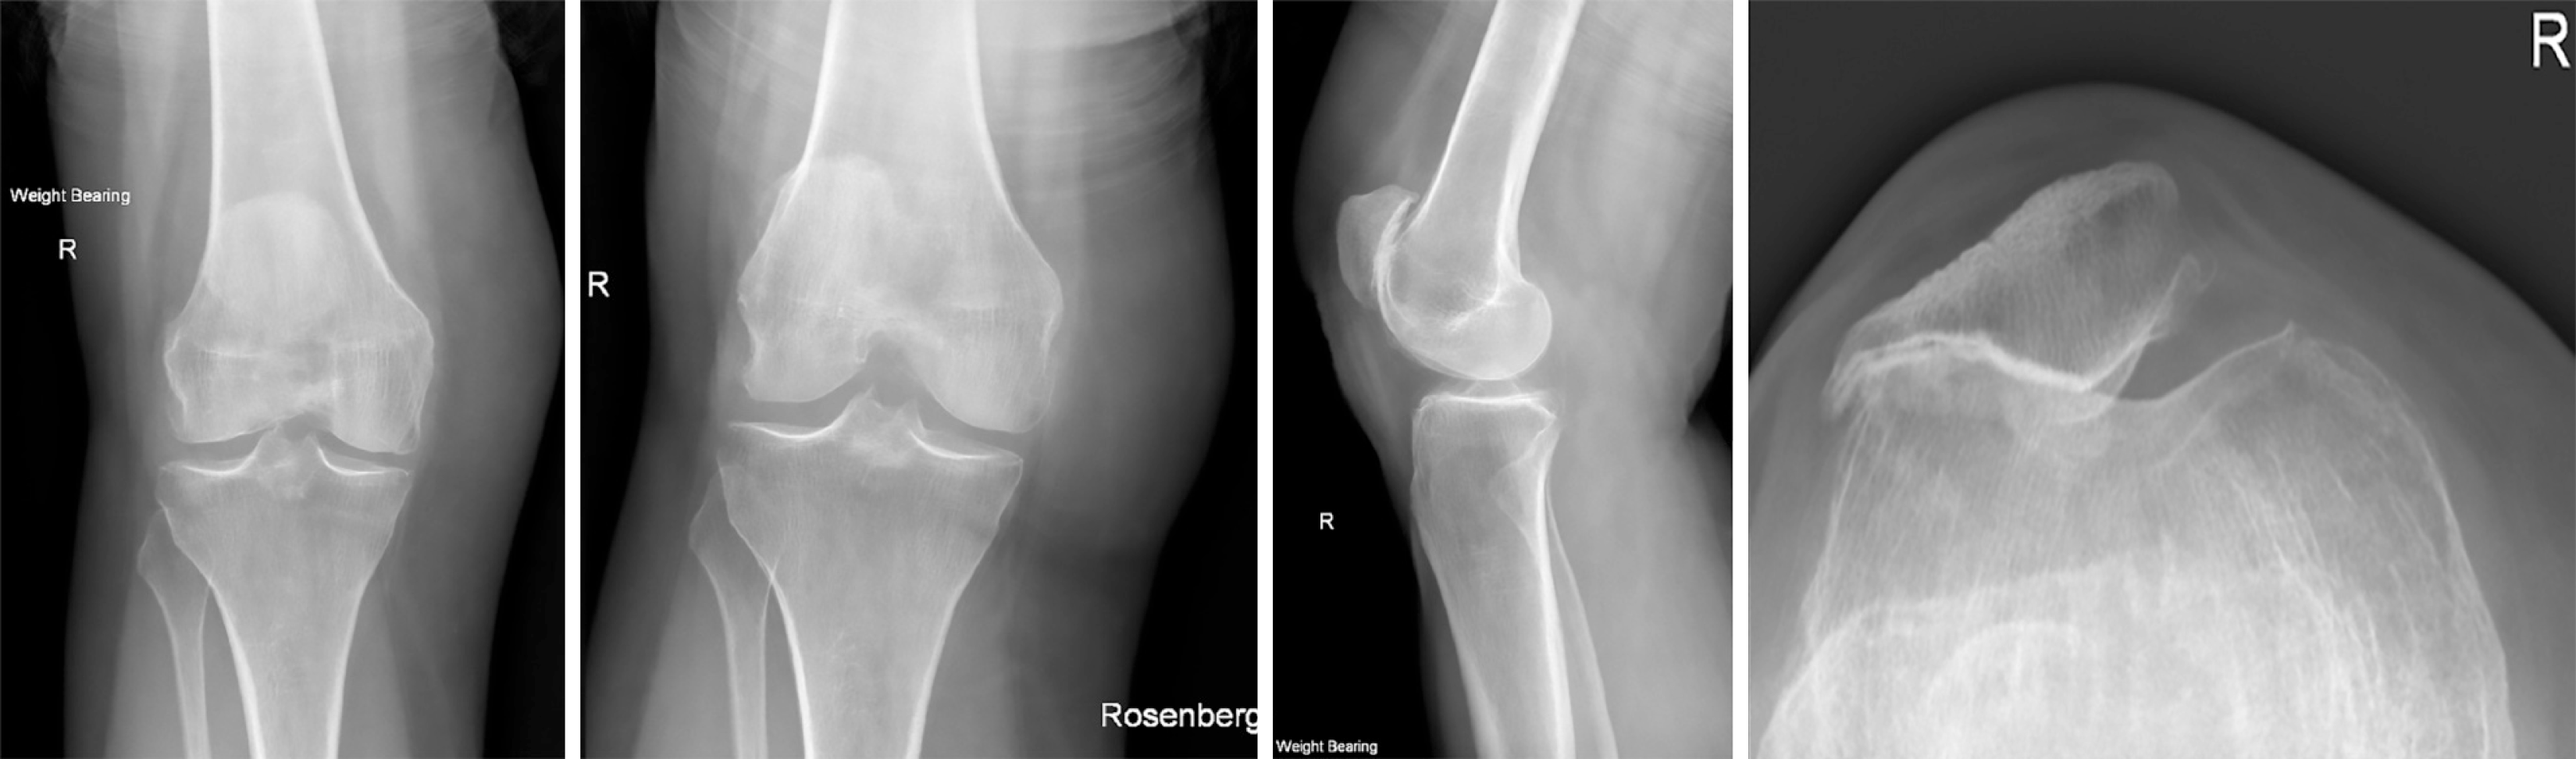

Figure 1 Initial X-ray and computed tomography.

A: Lateral knee X-ray demonstrating the inferior patella dislocation; B: Sagittal right knee computed tomography reconstruction showing a small depressed femoral trochlear fracture (white arrow) with an unchanged patella position; C: Axial right knee computed tomography reconstruction showing the mildly depressed femoral trochlear fracture (white arrow).